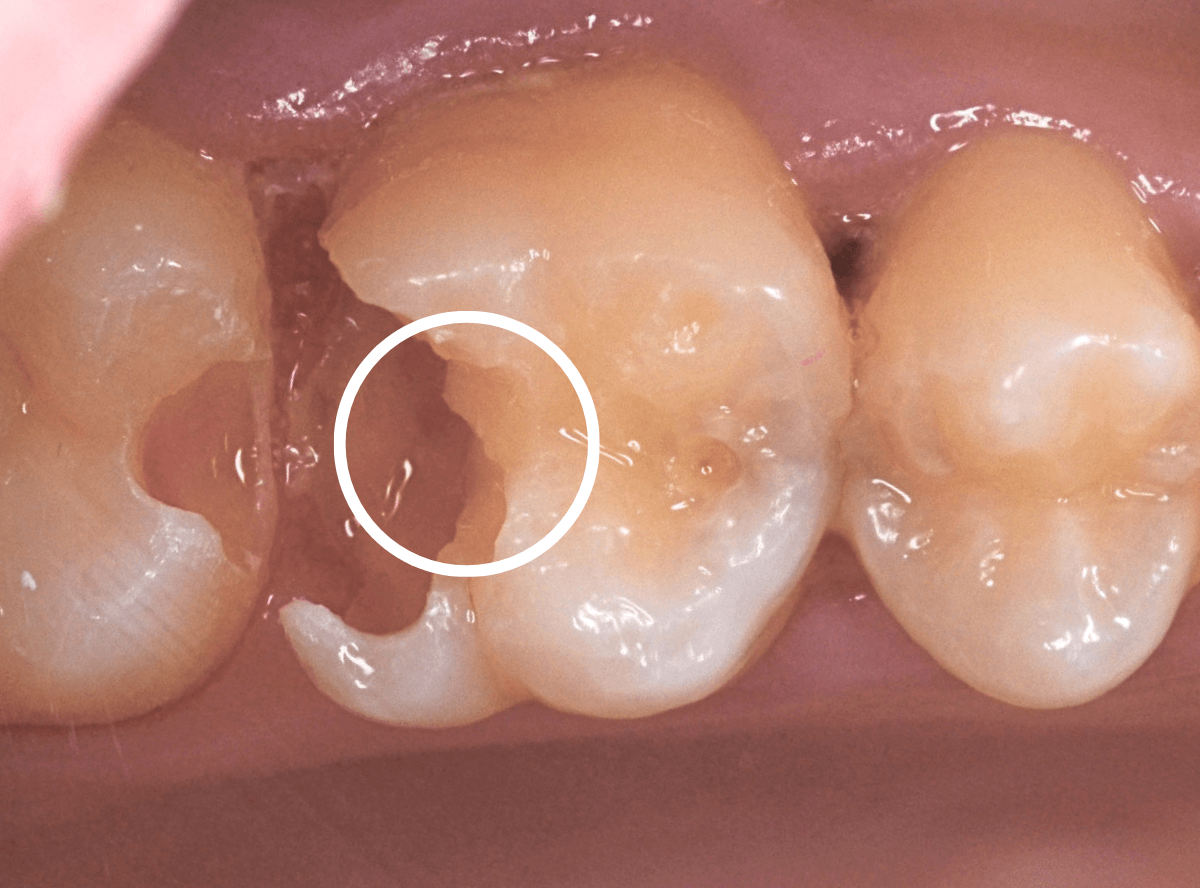

Case.13 歯と歯の間の虫歯が4本続いたケース

他の歯の虫歯の治療で来院された方で、下の歯の奥歯に虫歯が見つかった方です。

レントゲン写真で、歯と歯の間が虫歯になっているのがわかります。

手前の歯の状況です。

〇部のやっと黒く見えている部分が虫歯です。

少しずつ歯を削って確認します。

虫歯が出てきました。

全ての虫歯を除去したところです(薄く茶色に残っている部分は虫歯ではないです)。

かなり歯を削る必要があったのがわかるかと思います。

後ろの歯の状況です。

〇部に虫歯がある他に、矢印部、歯と歯の間に物がつまっているのが見えます。

このような状況の時は、中で大きな虫歯になっている事が多いです。

慎重に歯を削ります。

想像通り、大きな虫歯がでてきましたね。

治療してあった手前の歯のセメントの部分も外して、全ての虫歯を除去しました。

このように、自覚症状がなくても、虫歯は知らない間に深く広く進行している事が多いです。

くれぐれも自己判断はせず、定期検診するようにしてください。